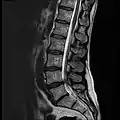

MRI lumbar spine with degeneration (sagittal T2 FRFSE)

MRI lumbar spine with degeneration (sagittal T1 FSE)

MRI lumbar spine with degeneration (sagittal FAST STIR)- MRI lumbar spine pre-hemilaminectomy (sagittal T2 FRFSE)